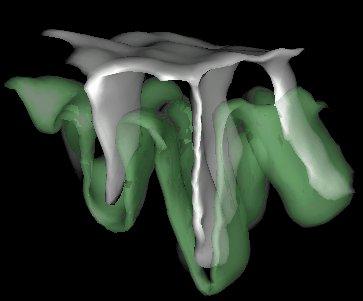

4. Last step, the detection of the putative burried gyri. The goal is to add into the cortex folding representation the necessary information to study the sulcal root notion. We are aiming indeed at defining a model of the cortical folding patterns built upon indivisible elementary units that may correspond to the first folds appearing during in utero life. This research program wants to overcome the weaknesses of the usual descriptions of the sulcus interruptions, a phenomenon which can even occur for the central sulcus:

We try to split the central sulcus at the level of the middle "pli de passage", which defines the two underlying sulcal roots. Viewed from beneath:

The simple surfaces are split into several pieces when depth variations or high values of the Gaussian curvature are clues of some putative gyrus. The current procedure is still far to be fully satisfying. Current efforts to improve it may be found in: